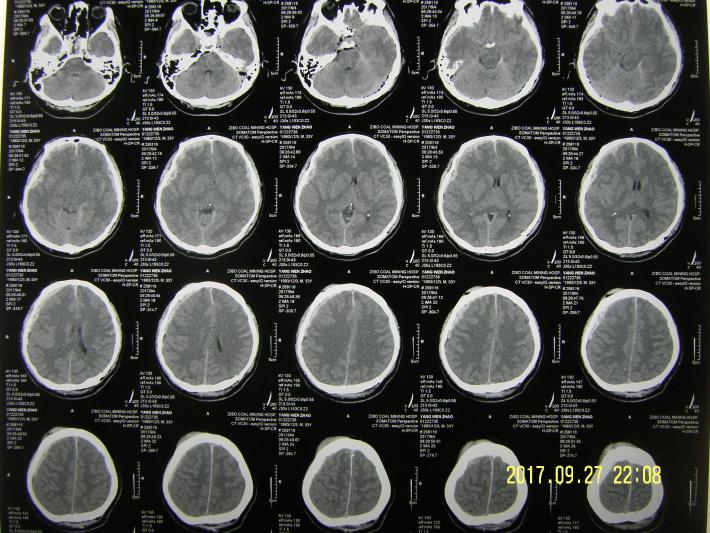

CT示双侧额颞部硬膜下血肿,弥漫性脑肿胀,蛛网膜下腔出血,多发头皮血肿。

术后1天,双瞳孔恢复正常等大,但仍处于昏迷状态,CT复查示,血肿清除满意,左额叶迟发挫裂伤灶,右颞抌叶低密度梗死灶,考虑术前脑疝,导致外伤性大脑后动脉供血区梗死。行脱水,抗炎,神经营养,脑保护,维护水电平衡,防治并发症等治疗。

术后7天CT示,尚处于脑水肿期,但环池,三脑室显示有改善。

术后13天CT示,皮下积液及左侧硬膜下积液,给予局部骨窗适当加压包扎,注意纠正头位及体位。

术后24天CT复查示,脑水肿基本消退,额叶挫裂伤灶明显收收,患者神志转清,有遵嘱动作,一月后出院康复。